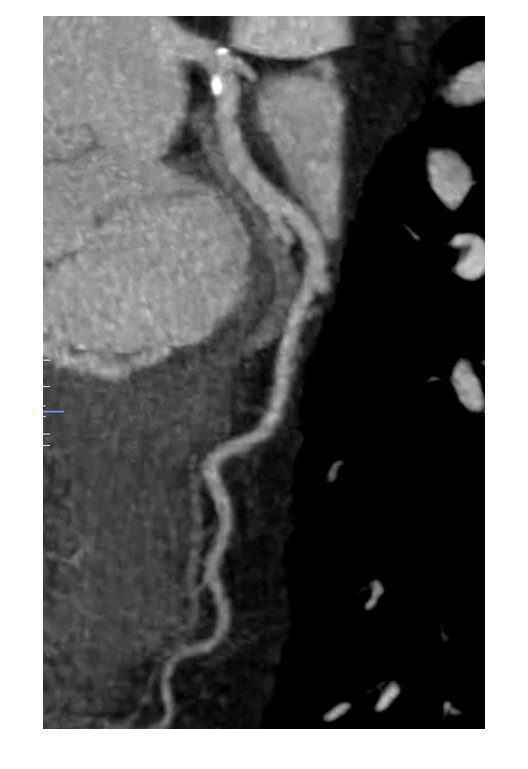

A coronary CT angiogram is ordered which showed a left dominant system and evidence of non-obstructive plaque (figures I-III). Coronary calcium score is 189, which is > 95th percentile for age/gender/race (see table 1). Her Segment Involvement Score (SIS) is 3, Segment Stenosis Score (SSS) is 0 and CT-Leaman Score (CT-LeSc) is 9 Smoking cessation is recommended.

Figure I: Coronary CTA showing LAD with calcified plaque (yellow arrow). Plaque in LCX (red arrow) and LM (blue arrow) can also be seen

Figure II: Coronary CTA showing calcification in the proximal circumflex artery